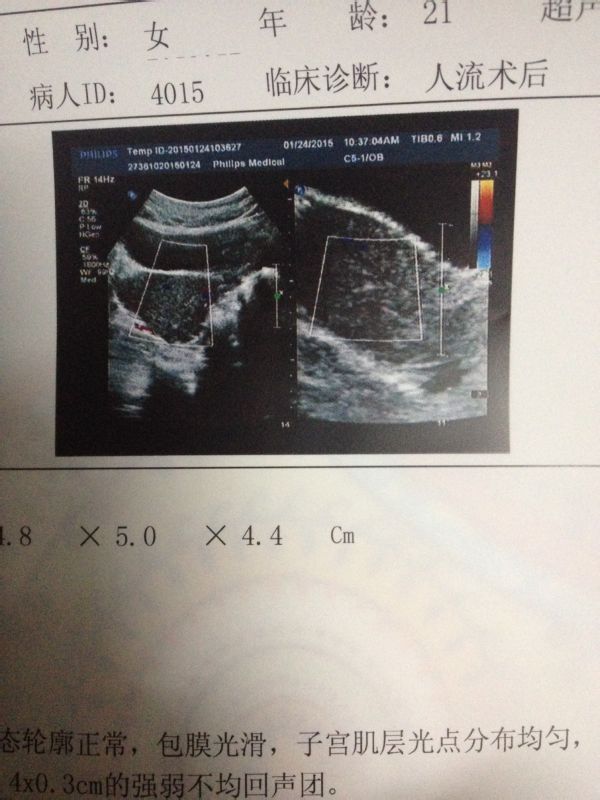

痛人流后未出血,一周后复查宫腔内异常回声,盆腔积液  做完无痛人流后没有流血,医生给开的五加生化胶囊和金英胶囊,九天后复查,B超显示:子宫切面大小形态轮廓正常,包膜光滑,子宫肌层光点分布均匀,其内未见明显异常回声,宫腔内可见0.4X0.3cm的强弱不均回声团。双侧附件区未见明显异常回声。子宫后方可见0.6cm的液性暗区CDFI:子宫及双侧附件区未见异常血流信号.检查提示:宫腔内异常回声、盆腔积液这是怎么回事?严重吗?